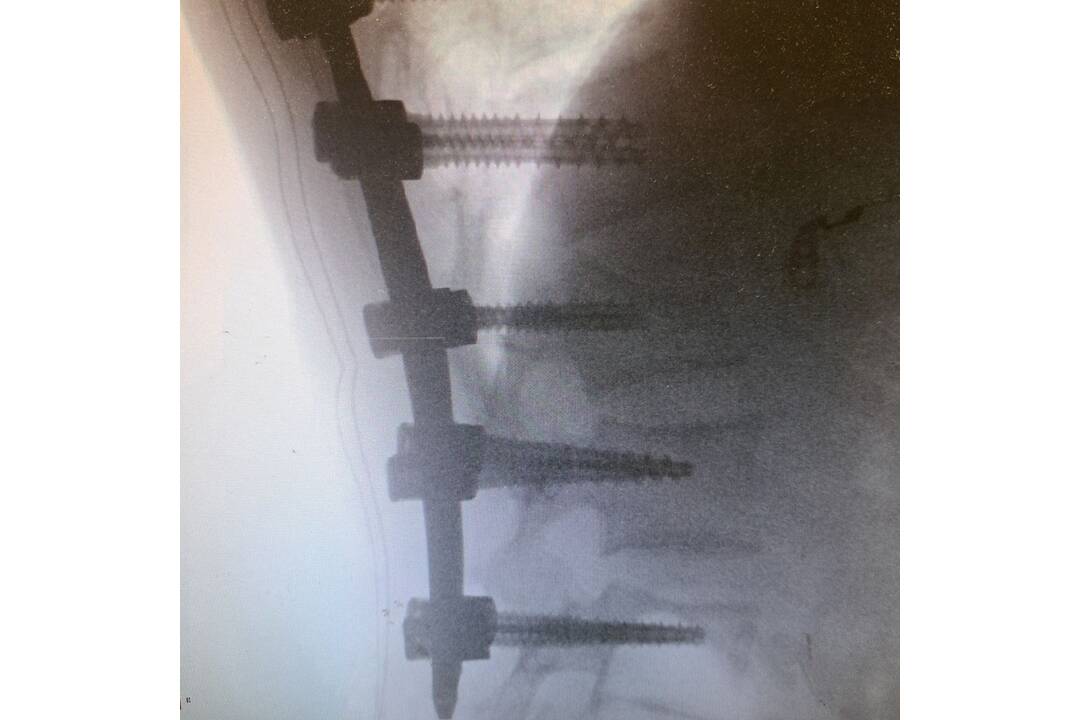

FOTO: Neurochirurgovia NÚDCH operovali vážne úrazy chrbtice, deti mohli skončiť na vozíku

FOTO: Neurochirurgovia NÚDCH operovali vážne úrazy chrbtice, deti mohli skončiť na vozíku, foto 3

Zdroj: Facebook/Národný ústav detských chorôb